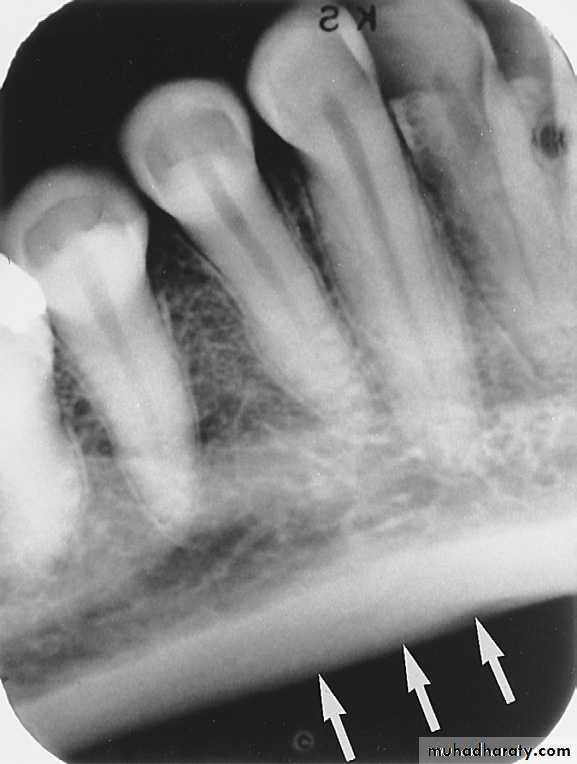

NUTRIENT CANALS

:

Nutrient canals carry a neurovascular bundle and appear as radiolucent lines of fairly uniform width. They are most often seen on mandibular periapical radiographs running vertically from the inferior dental canal directly to the apex of a tooth or into the inter dental space between the mandibular incisors.